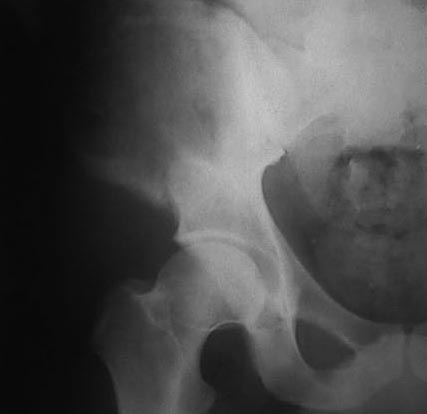

Могу пока выложить еще снимки и показать хронологию данного процесса и его прогрессирование, первый снимок был 2011 года. Вот этот 2009

И 2010 год

Также структуру поражения кости можно увидеть на обычных рентгенограммах таза или Компьютерно-Томографических срезах. Трехмерные снимки, кроме красивой картины, не добавляют информации, и самым главным информативным является МРТ, которая покажет структуру ячеек.